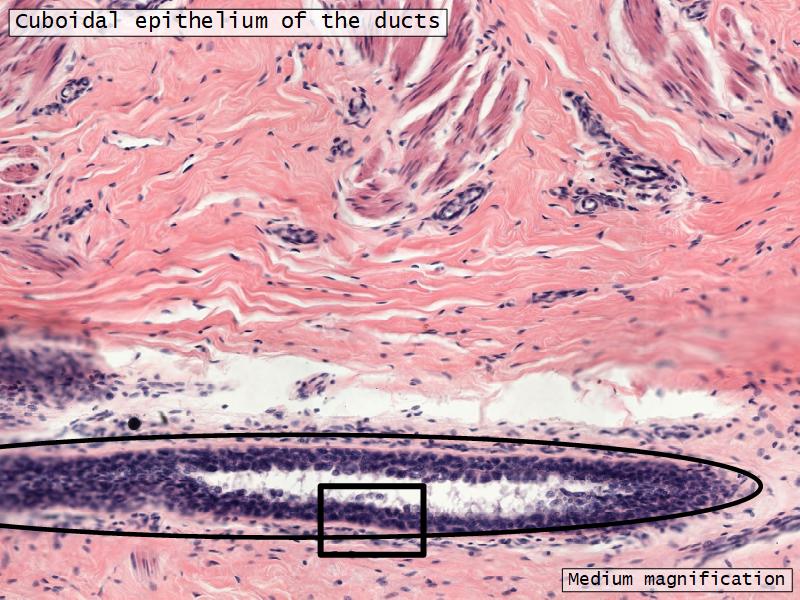

What epithelium are associated with ducts?Q03 - 3

What epithelium are associated with ducts?

Cuboidal epithelium

Mammary gland

Write short notes describing the structure of the mammary gland.

(5)

Mammary gland

- Compound tubuloalveolar gland

- 12 - 20 glands

- Each with own lactiferous duct

- Each with own lactiferous sinus

- Opens on skin at apex of nipple

Structures

List the structures and cells found in the mammary gland.

Structures

- Lactiferous sinuses

- Stratified squamous near opening on skin

- Stratified cuboidal other parts

- Lactiferous ducts

- Stratified cuboidal

- Myoepithelial cells

- Underlie lactiferous ducts in most areas

- Basal lamina

- Separate epithelial components from stroma